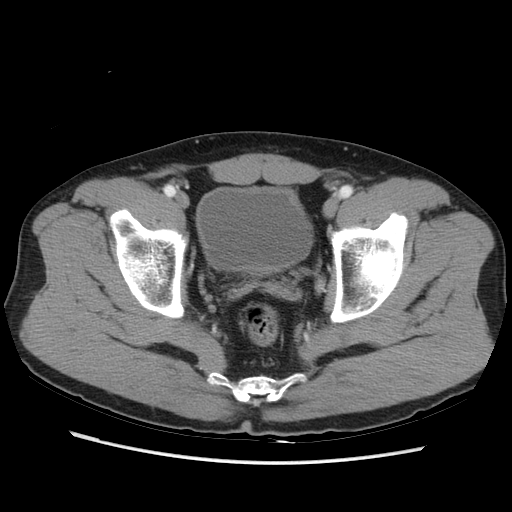

One hundred consecutive IC patients were investigated by symptom score, urodynamic study, cystoscopic hydrodistention, and bladder CT study. The BWT is divided into smooth (n=49), focal thickness (n=15), and diffuse thickness (n=36) subtypes, which are demonstrated in Figure 1.

Figure 1. Subtypes of BWT demostrated on CT